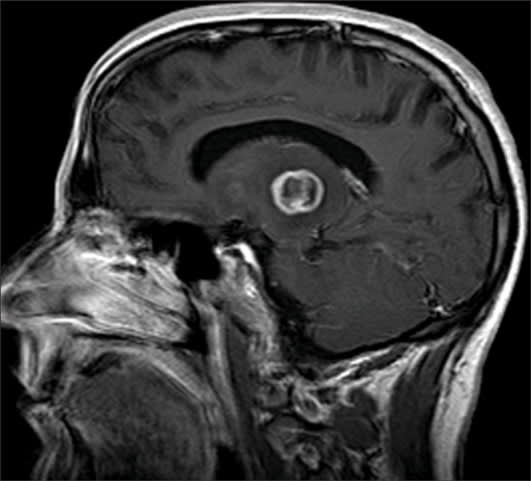

Visual acuity was reduced to counting fingers in the right eye and 20/30 in the left eye. The right pupil was 4 mm and minimally reactive, while the left pupil was briskly reactive. There was a 4+ right relative afferent pupillary defect. Confrontation visual fields revealed a central relative scotoma in the right eye and were full in the left eye. Extraocular movements were full in both eyes. Intraocular pressure was 21 mm Hg in the right eye and 17 mm Hg in the left eye. External ocular examination revealed leukocoria of the right eye (Figure 1). Slit-lamp examination revealed diffuse keratic precipitates of the right eye with 3+ cell/flare in the anterior chamber. Dilated fundus examination of the right eye revealed a yellow-white macular lesion associated with severe vitritis and perivasculitis (Figure 2). Slit-lamp and dilated fundus examinations of the left eye were unremarkable. Magnetic resonance imaging of the brain revealed a ring-enhancing lesion of the left thalamus with surrounding edema and midline shift (Figure 3). Anti-Toxoplasma gondii titers were immunoglobulin G-positive and immunoglubolin M-negative. Western blot analysis for human immunodeficiency virus (HIV) antibody was positive and the CD4 helper T-cell count was 14 cells/mm3.

Figure 3. Magnetic resonance image of the brain at presentation showing a ring-enhancing lesion of the left thalamus.

The differential diagnosis of necrotizing retinitis in patients with AIDS includes: toxoplasmosis, cytomegalovirus retinitis, acute retinal necrosis, progressive outer retinal necrosis, and endogenous fungal endophthalmitis. Neuroimaging of our patient revealed the classic asymmetric "target" sign, which helped to confirm our diagnosis of ocular toxoplasmosis. A diagnosis of toxoplasmosis was further supported by reduction in the size of the patient's retinal and cerebral lesions, as well as resolution of his intraocular inflammation with antiparasitic drug therapy.

Intracranial toxoplasmosis is the most common mass lesion in patients with AIDS with a predilection for the basal ganglia, thalamus, and corticomedullary junction.9 Intracranial toxoplasmosis is considered to be diagnostic for AIDS and may be its initial manifestation. Patients may present with focal neurologic deficits, seizures, or altered level of consciousness. Cerebral toxoplasmosis may, as in our case, present as a focal lesion, or it may present as a diffuse encephalitis.